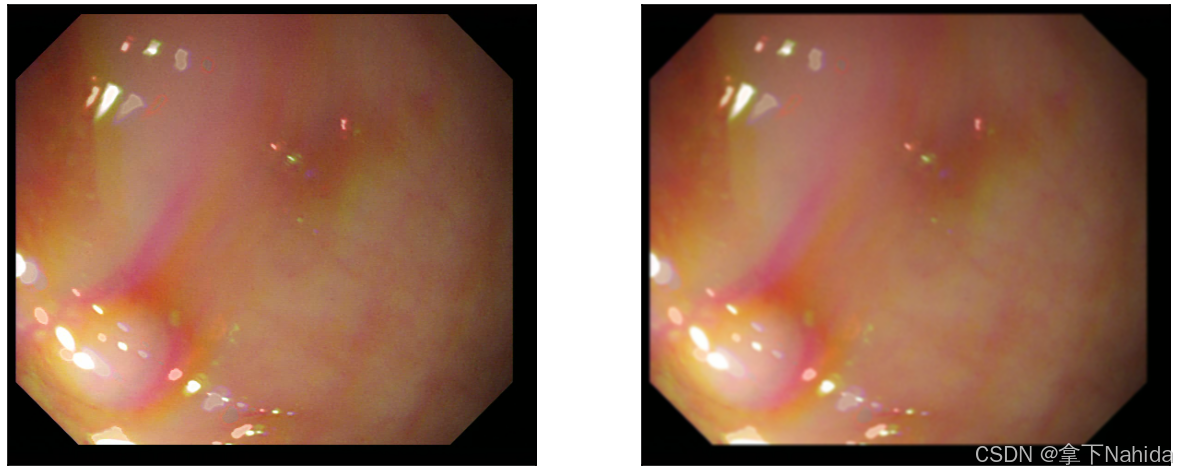

a.均值滤波

均值滤波是最简单的线性平滑滤波方法,它通过计算窗口内所有像素的平均值来代替中心像素的值,以此达到去除噪声的效果。

实例图如下。

看起来显得变得更模糊了,图像的颜色区间变化不那么尖锐,这样把噪点作出处理的同时牺牲了一定清晰度。